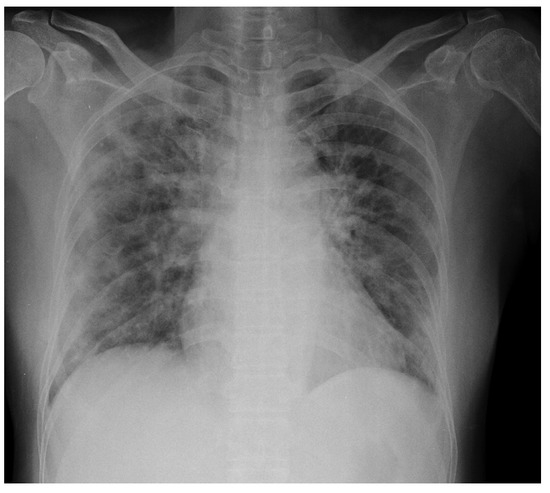

For a more intuitive understanding, we visualize a sample of each category in Figure 9, Figure 10 and Figure 11.

Figure 9. Covid sample: X-ray Image dataset.

Applsci 13 00454 g009